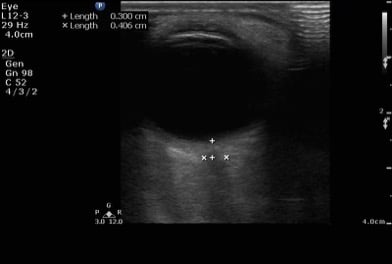

- Figure 4. Normal optic nerve sheath diameter measured 3mm from the insertion site of the optic nerve. Then it is measured transversely. Normal optic nerve sheath diameter in an adult is <5 mm.

- On ultrasound, a normal optic nerve sheath measures up to 5.0 mm in diameter. The ONSD is measured 3mm posterior to the globe for both eyes.

- A position of 3mm behind the globe is recommended because the ultrasound contrast is greatest, and the results are more reproducible.

- Two measurements are averaged.

- An averaged ONSD > 5 mm in adults is considered abnormal and elevated ICP should be considered.4

- An averaged ONSD > 4.5 mm in children (1-15 years) and > 4mm (less than 1 year of age) are abnormal.4